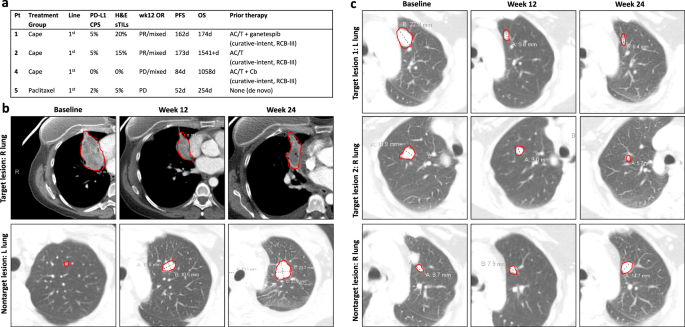

Activity in metaplastic TNBC

Four patients with metaplastic TNBC were enrolled, three in the capecitabine arm, and one in the paclitaxel arm. Responses are summarized in Fig. 5. We observed two clinical responses (PR at 12 weeks), both in the capecitabine arm (Fig. 5). Response durations were 162 and 173 days. Images of both patients showed evidence of mixed response, with some lesions shrinking and others growing (Fig. 5B). Both patients had tumors with borderline PD-L1 CPS scores (case 1: CPS = 5, case 2: CPS = 5) which would be considered PD-L1-negative using the paradigm established by the Keynote-355 trial14. One of the 2 non-responding tumors (patient 3, capecitabine arm) exhibited mixed tumor growth and regression, but overall PD by RECIST1.1 criteria. Additional details regarding these cases are summarized in a recently published case series15.

a Summary of clinical findings of metaplastic patients; b radiographic response of patient 1. Findings overall demonstrate a partial response, but with an initial non-target left lung nodule gradually increasing in size; c radiographic response of patient 2, showing a mixed, but overall partial response. Cape capecitabine, CPS combined positive score, H&E hematoxylin & eosin, sTILs stromal tumor-infiltrating lymphocytes, PR partial response, PD progression of disease, R right, L left, AC/T doxorubicin, cyclophosphamide, and paclitaxel, Cb carboplatin, RCB residual cancer burden score.